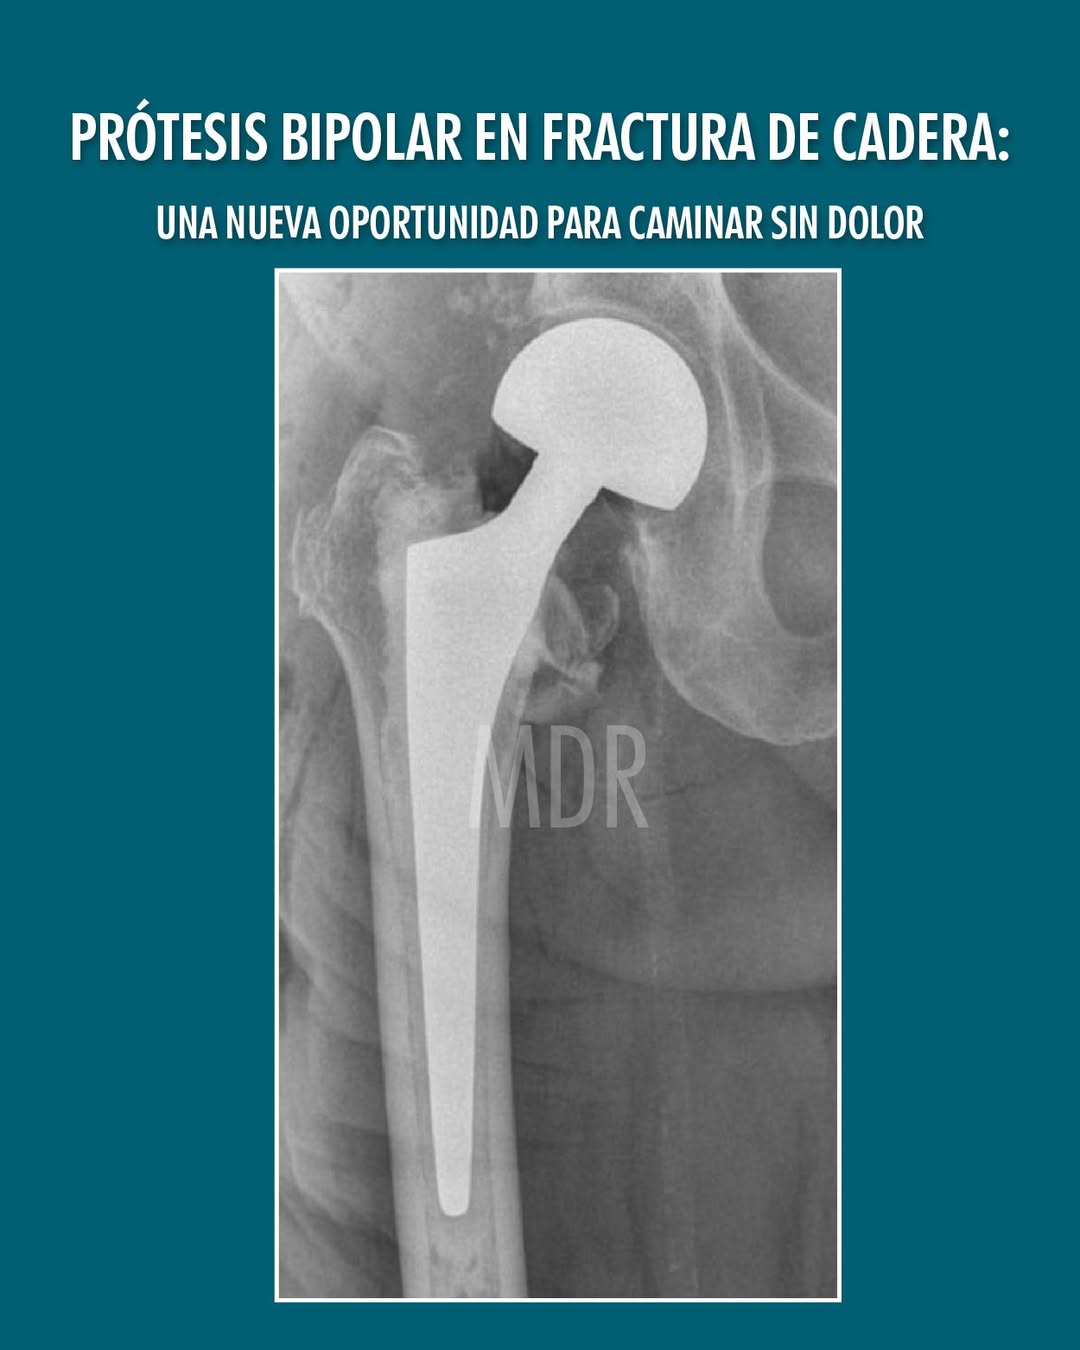

Prótesis Bipolar en Factura de Cadera

Una nueva oportunidad para caminar sin dolor